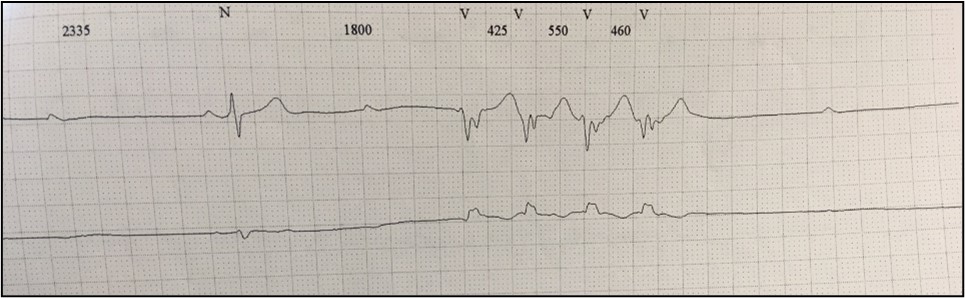

In 2012 the patient was admitted presenting with dyspnea on moderate exertion. His ECG showed complete heart block with a narrow QRS rhythm at 40 bpm, which persisted after Bisoprolol washout. Also, a significant burden of PVC and NSVT episodes were detected during the monitoring (Figure 2).

Clinical case_ Fig 2 - The importance of early etiologic diagnosis of dilated cardiomyopathy.jpg